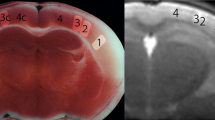

Pathological correlation could be done in an 83-year-old woman with cardioembolic cerebral infarction in the territory of the right middle cerebral artery. She presented with left hemiparesis, and her medical history included atrial fibrillation. T1-weighted imaging obtained at 27 days after the onset showed curvilinear hyperintense lesions in the cerebral cortex (Fig. 3a). She died at 94 days after MR examination. T1-weighted imaging of the brain at autopsy showed curvilinear hyperintense lesions in the cerebral cortex (Fig. 3b). Autopsy disclosed infarction of the right cerebral hemisphere (Fig. 3c). Histologically, necrotic debris filled the entire cortex in the infarcted area (Fig. 3d). Small numbers of fat-laden macrophages were present. Abundant reactive astrocytes encircled the necrotic zone of the cortex. The necrotic debris in the infarcted cortex was negative for Prussian blue staining, suggesting that extravasation of blood had not occurred.

An 83-year-old woman with cerebral infarction in the territory of the right middle cerebral artery. a T1-weighted image obtained 27 days after the onset shows curvilinear hyperintense lesions in the cerebral cortex. b Postmortem T1-weighted image shows curvilinear hyperintense lesions in the cerebral cortex. c Pathologic specimen obtained in the area that corresponds to b shows infarction in the territory of the right middle cerebral artery. Infarcted white matter with cystic change is pale. A relatively dense cortical lesion in the infarct zone corresponds to the curvilinear hyperintense area on T1-weighted images. d Histological examination reveals necrotic debris replacing the entire cerebral cortex. A thin rim of preserved subpial tissue overlies a zone of cortex in which necrotic debris is identified. A cavity surrounded by a dense layer of reactive astrocytes is noted in the white matter

Anemic infarction describes a zone of coagulation necrosis or pan-necrosis that is often secondary to arterial occlusion [12, 17–19]. The appearance of areas of coagulation necrosis is delayed. In the chronic stage, reabsorption of necrotic debris takes place, and the necrotic tissues are replaced by a cavity filled with fluid [18, 19]. Our pathological correlation study demonstrated that curvilinear cortical lesions corresponded to areas of severe pancortical necrosis that were tantamount to infarction. The cellular infiltrate replacing the neuronal layers comprised a mixture of astrocytes and macrophages.

Our MR-pathological correlation study in an autopsied patient with chronic cerebral infarction demonstrated that cortical curvilinear lesions showing hyperintensity on T1-weighted images corresponded to necrotic debris in the entire cortex. A concentrated protein solution in the necrotic debris is likely to show a shortened T1 relaxation time due to the macromolecular hydration effect. Negative for iron with Prussian blue staining indicates that hemorrhage did not occur. Although high cellularity may be attributed to T1-shortening, a mixture of astrocytes and macrophages was seen at the periphery of the infracted area. Thereafter, we suggest that a main cause of T1 shortening caused in the infarcted cortex was denatured protein in the necrotic debris. Since cortical T1 hyperintensity is marked during the subacute period, biochemical factors, including paramagnetic compounds such as manganese ions, and free radicals produced by macrophages, may also contribute to T1-shortening in the earlier phase [20, 21]. Alternatively, deposition of fat-laden macrophages, or cellular components of necrotic tissue, may be implicated in T1 shortening [12, 22]. Thus, a T1 high signal is likely to represent the consequence of acute necrosis.